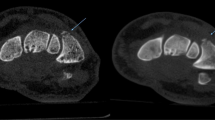

Both reader 1 and reader 2 missed one same ankle fractures on CD-CT (Fig. 2). Reader 1 missed two ankle fractures, one shoulder fracture and two wrist fractures on bone algorithm ULD-CT, while missed two ankle fractures, one shoulder fracture and three wrist fractures on soft tissue algorithm. However, when the two algorithms reconstruction methods were combined, the diagnostic performance improved. Reader 1 only missed two ankle fractures when using both bone and soft tissue algorithms reconstruction images. Reader 2 presented a similar scenario: he missed two ankle fractures, one shoulder fracture and three wrist fractures on bone algorithm ULD-CT, while missed two ankle fractures, one shoulder fracture and two wrist fractures on soft tissue algorithm ULD-CT. Combining both bone and soft tissue algorithms ULD-CT, he only missed two ankle fractures. In addition, reader 2 misdiagnosed one wrist fractures on soft tissue algorithm ULD-CT.

After a fall, a 54-year-old male reported to the emergency department with right shoulder joint pain and limited mobility for 1 day. On ULD-CT bone reconstruction images (A) reader 2 missed the avulsion fracture of the humeral head (white arrows), but not on ULD-CT soft tissue reconstruction images (B) or the CD-CT images (C)